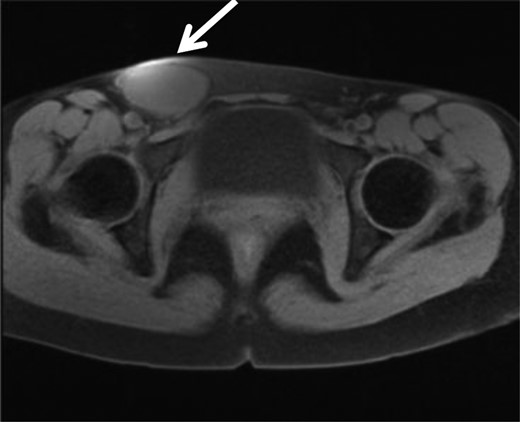

A 35-year-old woman was referred to our hospital for a painful right groin tumor which grew in size which was not related to her menstrual cycle. With the diagnosis of inguinal endometriosis, she had been treated with two cycles of low-dose birth-control pills, and five cycles of genogest previously, but the groin was increased in size to 5-cm with pain. In her past medical history, no history of gynecologic problems and specifically no dysmenorrhea nor dyspareunia were recorded. In the right groin, there was a 5-cm bulge which was detected as a homogeneous hypoechoic subcutaneous tumor and measured 53 × 29 mm by ultrasonography (Fig. 1). Her serum cancer antigen-125 was elevated to 95.4 U/ml (range <35 U/ml) before starting hormone therapy, and down to 40 U/ml when she came to our hospital even though the tumor size was unchanged. Magnetic resonance imaging (MRI) revealed a 6-cm unilocular tumor with internal high intensity in T1WI image which suggested internal bleeding (Fig. 2). We diagnosed the right inguinal tumor as a Nuck cyst. An inguinal approach was selected and after opening the skin and subcutaneous fat, a dark red tumor was founded which protruded from the femoral ring, in spite of our initial impression that the tumor was located along the round ligament (Fig. 3). After careful dissection, the tumor turned to be a unilocular cyst containing serous fluid, which was connected with the peritoneum through a string structure at the femoral ring, which was not connected with the abdominal cavity. The cyst was excised and the string structure was resected at the femoral ring. We inserted a plug into the extended femoral ring, and confirmed no other hernia. Her postoperative course was uneventful, and she was discharged on the first postoperative day. The histopathologic examination showed that mesothelial cells lined the wall of the cyst with degeneration, inflammation, hemorrhage, formation of hyperplastic collagen fiber and hemosiderosis without malignancy (Fig. 4). The immunohistochemistry [Calretinin(+)] confirmed the mesothelial origin of the cyst-lining cells and [CD10(+), ER(+), PgR(+)] suggested the endometrial origin of a few stromal tissue composing the cystic wall. As of 10 months after the operation, no recurrence of hernia or cyst has been encountered.

A 5-cm mass was confirmed over the right inguinal ligament by physical examination.

MRI showed a high intensity tumor in T1WI which suggest bleeding in the tumor, in the right inguinal region.